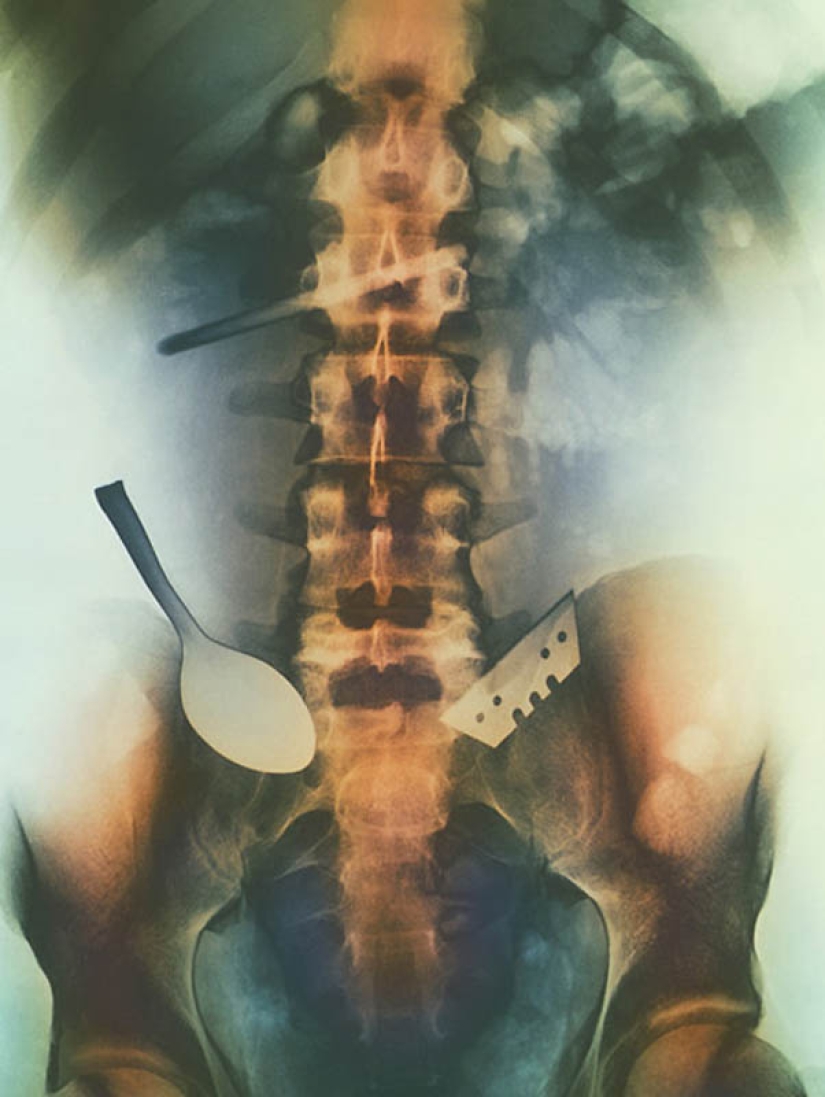

5. Color image of objects that the patient has swallowed and that are stuck in his intestines, including a spoon and a blade.